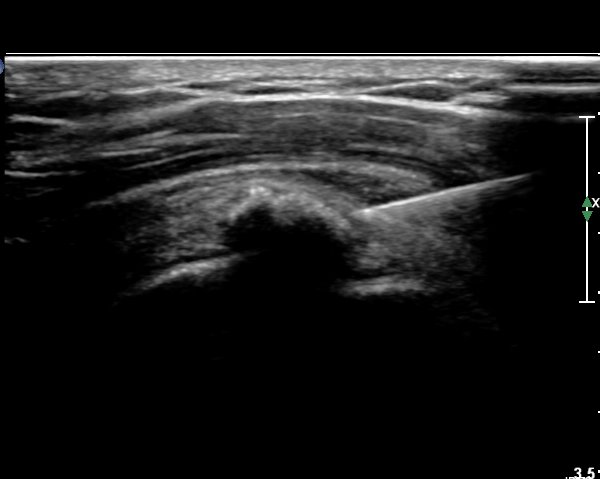

ÃÊÀ½ÆÄ ¼Ò°ß :  ±Ø»ó°Ç Á¾´Ü¸é°Ë»ç¿¡¼­ ÈĹæÀ½¿µÀ» º¸ÀÌ´Â °í¿¡ÄÚ ¼®È¸È­ µ¢¾î¸®°¡ °üÂûµÈ´Ù(»çÁø 1).